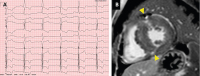

EKG-Veränderungen

Abbildung 1: (A): Typische EKG-Veränderungen: positiver Hypertrophie-Index, präterminale T-Negativierung links-präkordial und „Giant-T-Waves“ über der Vorderwand, (B): Late enhancement in den ventrikulären Insertionspunkten (Pfeile) bei HCM.